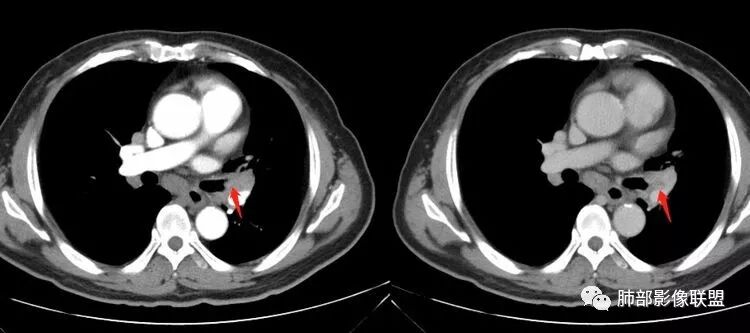

我们看这个主支气管的层面,主支气管明显受压,有变形的,但是软骨是没有突破的。

南边:那也就是说,这个纵隔淋巴结,它是没有影响到我们主支气管内部去的,周围有,可惜的膜部的增厚,我总心里不踏实,后面因为食道贴在一起啦。 因此这些淋巴结在主支气管层面是没有影响的。

这个区域明显就是一个支气管本身有问题。